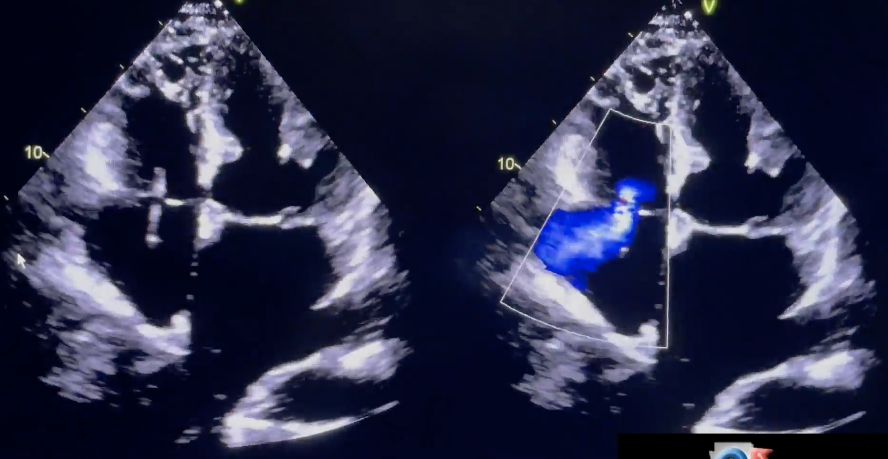

Pacer wire demonstrated passing through the?

TV to enter the RV

3D of the MV demonstrating?

Flail mitral leaflet